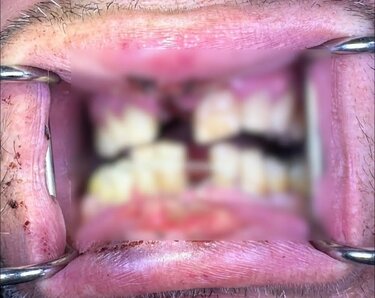

Ο άνδρας αρχικά μεταφέρθηκε στο Βενιζέλειο Νοσοκομείο Ηρακλείου και στη συνέχεια επισκέφθηκε ιδιώτη οδοντίατρο για την αποκατάστασή του. Τα τραύματα που υπέστη είναι σοβαρά καθώς όχι μόνο έσπασαν δύο από τα δόντια του, αλλά κουνιούνται και άλλα τέσσερα, τα οποία κινδυνεύει να χάσει. Παράλληλα, υπήρξαν τραυματισμοί στα ούλα και το στόμα του.

«Του έσπασαν δύο δόντια, ένα πάνω και ένα κάτω, και κούνησαν τα δύο κάτω πρόσθια δόντια και τα δύο πάνω. Από ότι μου είπε, εκείνη τη στιγμή έφυγε κάτι σαν οβίδα μπροστά και άρπαξε και η κουρτίνα φωτιά. Μετά, αιμορραγούσαν τα ούλα του και πήγε με ασθενοφόρο στο Βενιζέλειο Νοσοκομείο, όπου του παρασχέθηκαν οι πρώτες βοήθειες. Την επόμενη ημέρα, ήρθε σε εμένα και του ακινητοποίησα τα δόντια που κουνιούνταν, του έβγαλα ανάλογες φωτογραφίες και τώρα περιμένουμε να επουλωθούν οι πληγές. Ωστόσο τα άλλα τέσσερα που κουνάνε μπορεί να τα χάσει, δεν ξέρουμε αν θα σωθούν. Τώρα δεν μπορεί να ανοίξει εύκολα το στόμα για να δούμε σε τι κατάσταση είναι και τα υπόλοιπα».